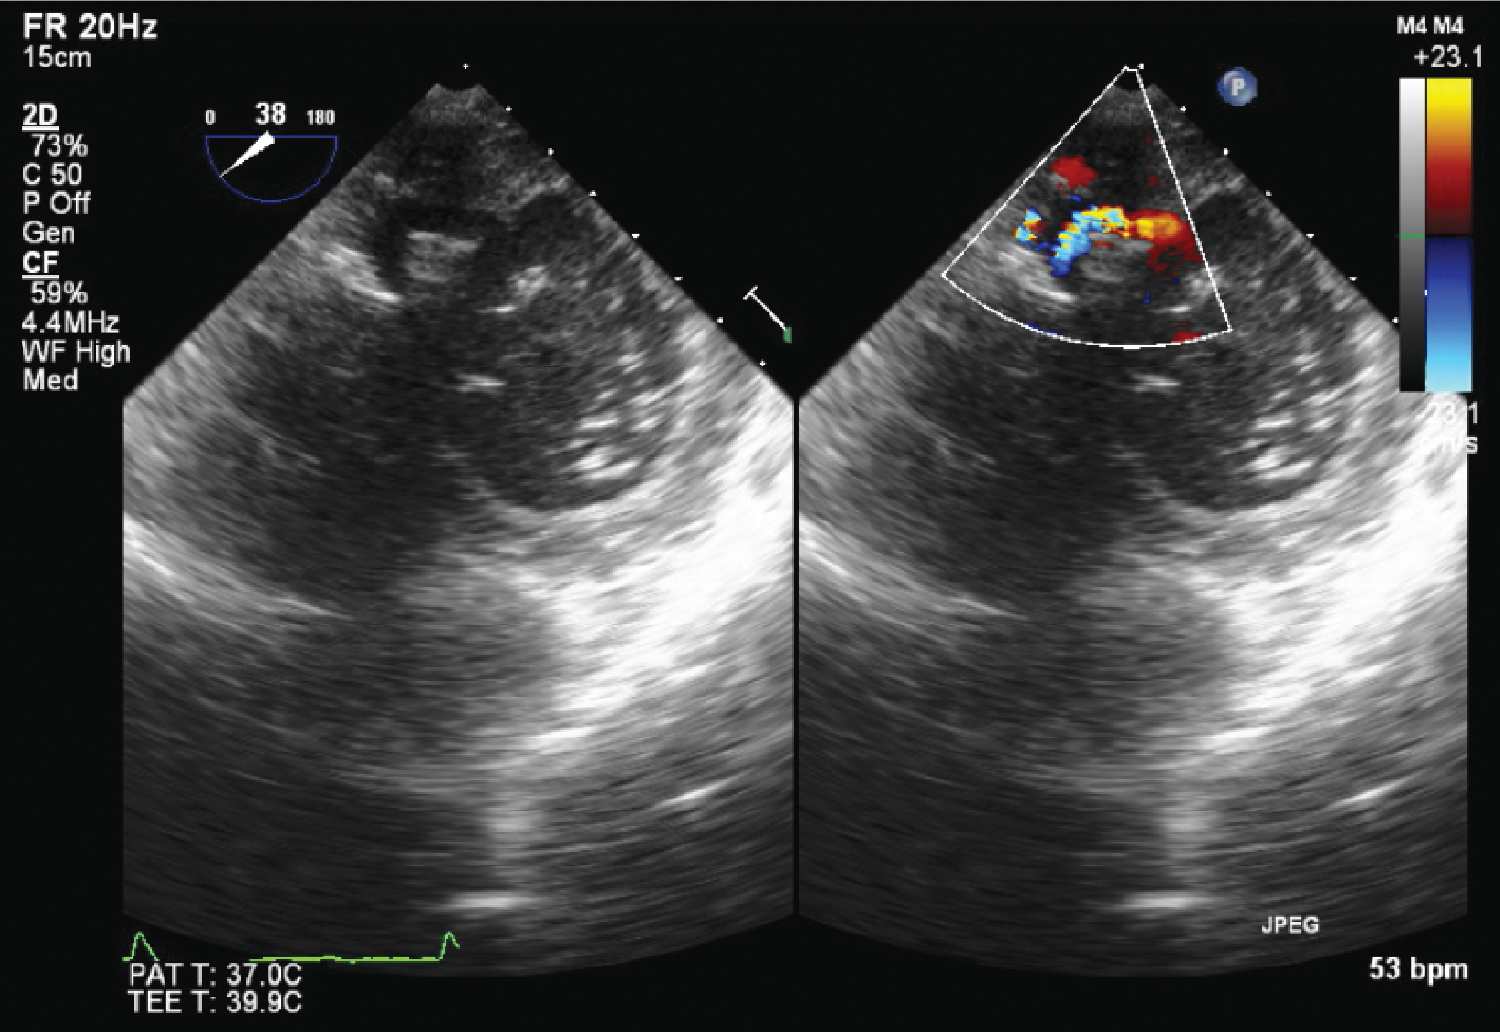

» Interpreting 2d echo results (97) 사진

Interpreting 2d echo results (97) 사진